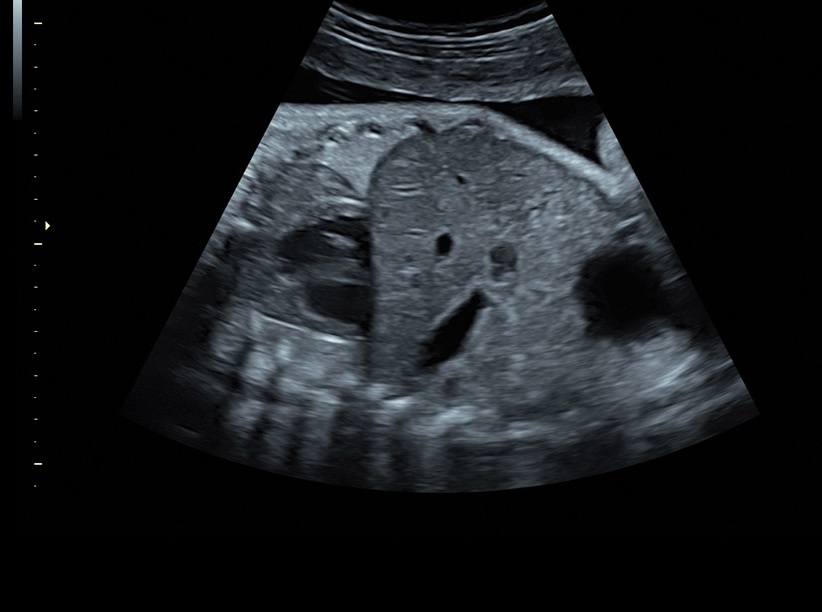

• Высокое качество изображений: Voluson S8 обеспечивает высококачественные изображения, позволяющие детально оценить состояние плода и обнаружить возможные патологии.

• Сложные инструменты для оценки качества плода: Сканер оснащен инновационными инструментами, позволяющими проводить детальную оценку состояния плода, включая его сердечную деятельность, анатомию и кровоток.

• Технология автоматической фетометрии в 2D режиме (SonoBiometry): Эта технология позволяет автоматически измерять бипариетальный размер, окружность головы, окружность живота, длину бедра и плеча плода, обеспечивая точные и надежные измерения.